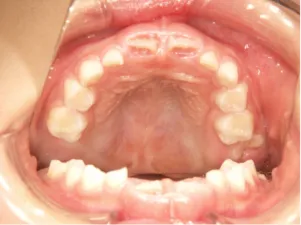

治療中⑤小3(9y2m):モノブロック装置(筋機能的咬合誘導装置)で永久歯の咬み合わせ治療へ移行

| 行ったご提案・診断内容 | 成長期に行う治療と咬合治療をご提案 受け口用ファンクショナルアプライアンス(写真②③)からスタートし、小2以降で上下顎の拡大・歯列弓の形態修正・前歯の並べ直し(写真④)を行いその後、モノブロック(筋機能的咬合誘導)装置(写真⑤)へ移行し、受け口の再発予防と永久歯を適切な咬み合わせに誘導し、必要によりマルチブラケット法へ移行する治療方法を提案しました。 成長期治療(成長時期にお口の環境を整える治療) 2年生以降から 咬合治療 |